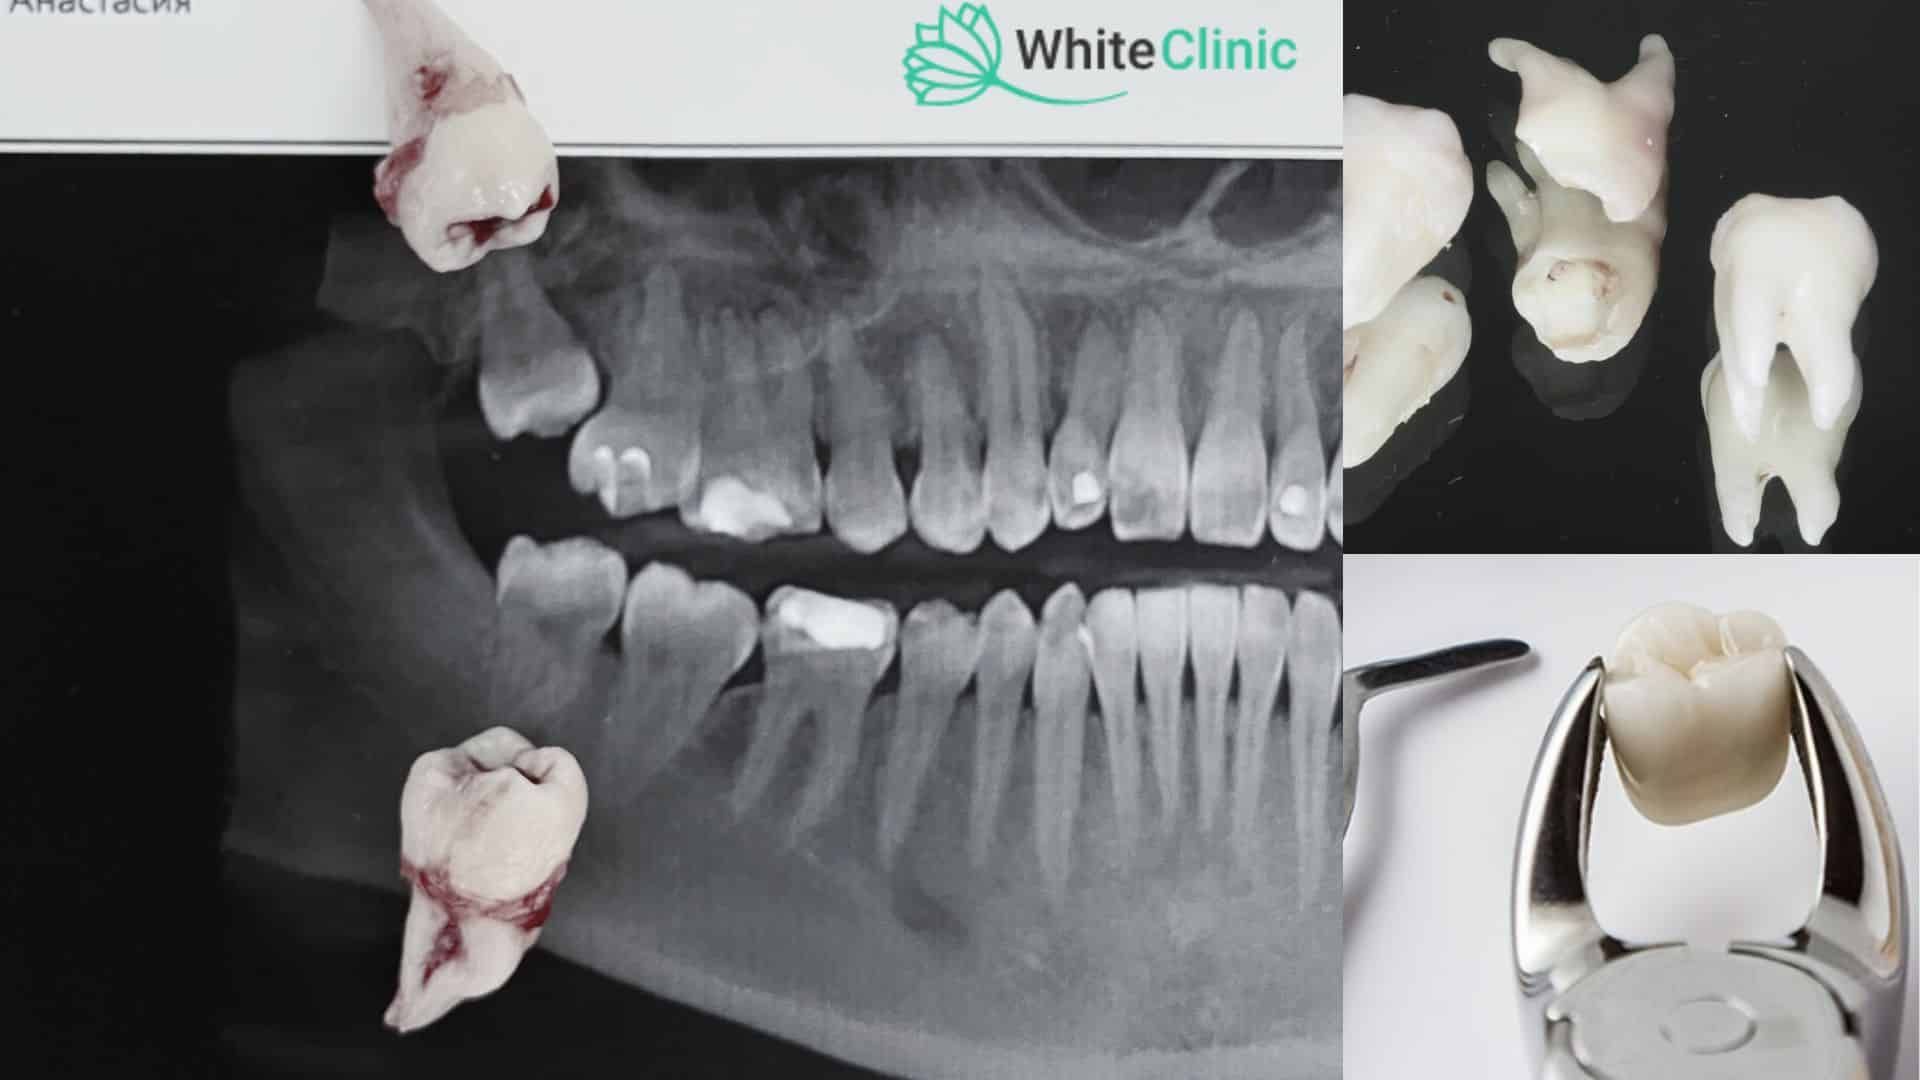

Перш за все, стоматолог проводить детальний огляд і діагностику, яка включає КТ щелепи. Це дозволяє оцінити положення нерва та як розміщені корені в 3d просторі. На цьому етапі також обговорюються варіанти лікування та видалення

Процедура видалення може бути простою або хірургічною. Просте видалення виконується, коли зуб мудрості повністю прорізався і доступний. Стоматолог використовує спеціальні інструменти для розхитування та видалення зуба.

У випадках, коли зуб мудрості частково прорізався або залишається під яснами, необхідне хірургічне втручання. Стоматолог може зробити невеликий розріз на яснах для доступу до зуба. Іноді зуб мудрості доводиться розділити на кілька частин для полегшення його видалення.

Ціна видалення зуба мудрості може варіюватися залежно від складності процедури, методу видалення, типу анестезії та інших факторів. У нашій клініці використовуються новітні методи видалення зубів. Ультразвуковий апарат – п’єзот Acteon забезпечує мінімально травматичне видалення без пошкодження зубного нерву, на відміну від бору (стоматологічний інструмент, який використовується при видаленні зубів). Важливо обговорити всі деталі та побажання з вашим стоматологом заздалегідь, щоб отримати точну оцінку вартості процедури.